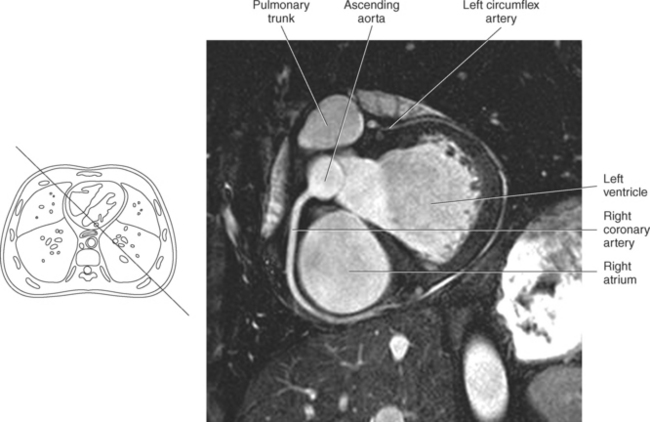

The right atrium forms the right border of the heart and receives deoxygenated blood from the body via the superior and inferior venae cavae and from the coronary sinus and cardiac veins that drain the myocardium. A small muscular embryonic appendage, the right auricle, projects upward and toward the left from the right atrium, covering the root of the aorta (Figure 6.40). The right ventricle lies on the diaphragm and comprises the largest portion of the anterior surface of the heart. It receives deoxygenated blood from the right atrium and forces it into the pulmonary trunk for conveyance to the lungs. Projecting off the inferior surface of the ventricular walls are conical-shaped projections of cardiac muscle called papillary muscles that anchor the cusps of the tricuspid valve to the right ventricle (Figure 6.39). The left atrium lies posterior to the right atrium and is the most posterior surface of the heart. It also has an embryonic appendage, the left auricle, that projects to the left of the pulmonary trunk over the superior surface of the heart. The left atrium receives oxygenated blood directly from the lungs via the four pulmonary veins (two on each side). The left ventricle forms the apex, left border, and most of the inferior surface of the heart. It receives oxygenated blood from the left atrium and pumps it into the aorta for distribution throughout the systemic circuit. The myocardium of the left ventricle is normally three times thicker than that of the right ventricle, reflecting the force necessary to pump blood to the distant sites of the systemic circulation (Figures 6.41 through 6.52). Two papillary muscles project from the ventricular walls to anchor the bicuspid valve to the ventricle (Figures 6.39 and 6.47).

Figure 6.43 Axial, T1-weighted MR scan of left atrium.

Key: RV, Right ventricle; LV, left ventricle; LA, left atrium; RA, right atrium.